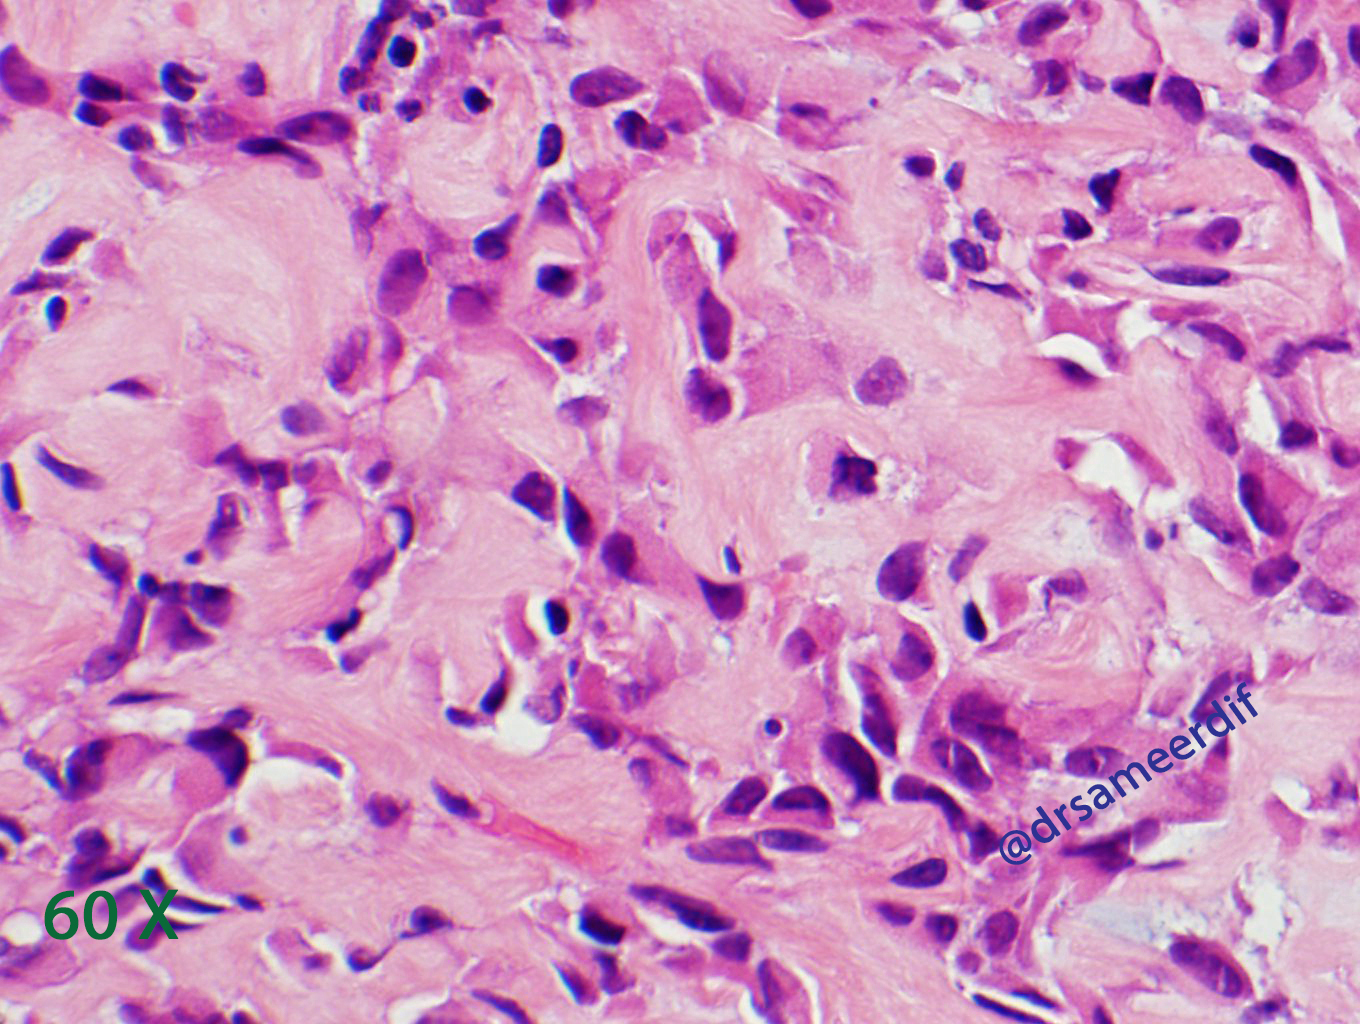

The current biopsy shows a densely hyalinized sclerotic matrix, with focal areas reminiscent of osteoid, lined by small to medium-sized epithelioid cells with clear to eosinophilic cytoplasm and bland nuclei. Mitotic figures are inconspicuous. By immunohistochemistry, the neoplastic cells are positive for MUC4, but negative for CK7, CK20, SATB2, and calcitonin. The morphology and immunohistochemical results are diagnostic of metastatic sclerosing epithelioid fibrosarcoma (SFE) from primary know SFE of the soft tissue.

- Nests and cords of small to medium size, round- oval nuclei with scant clear to pale cytoplasm

- Hyalinized stroma, which may resemble osteoid. Sometimes cartilaginous and osseous metaplasia may be seen and it may show focal myxoid change or calcification.